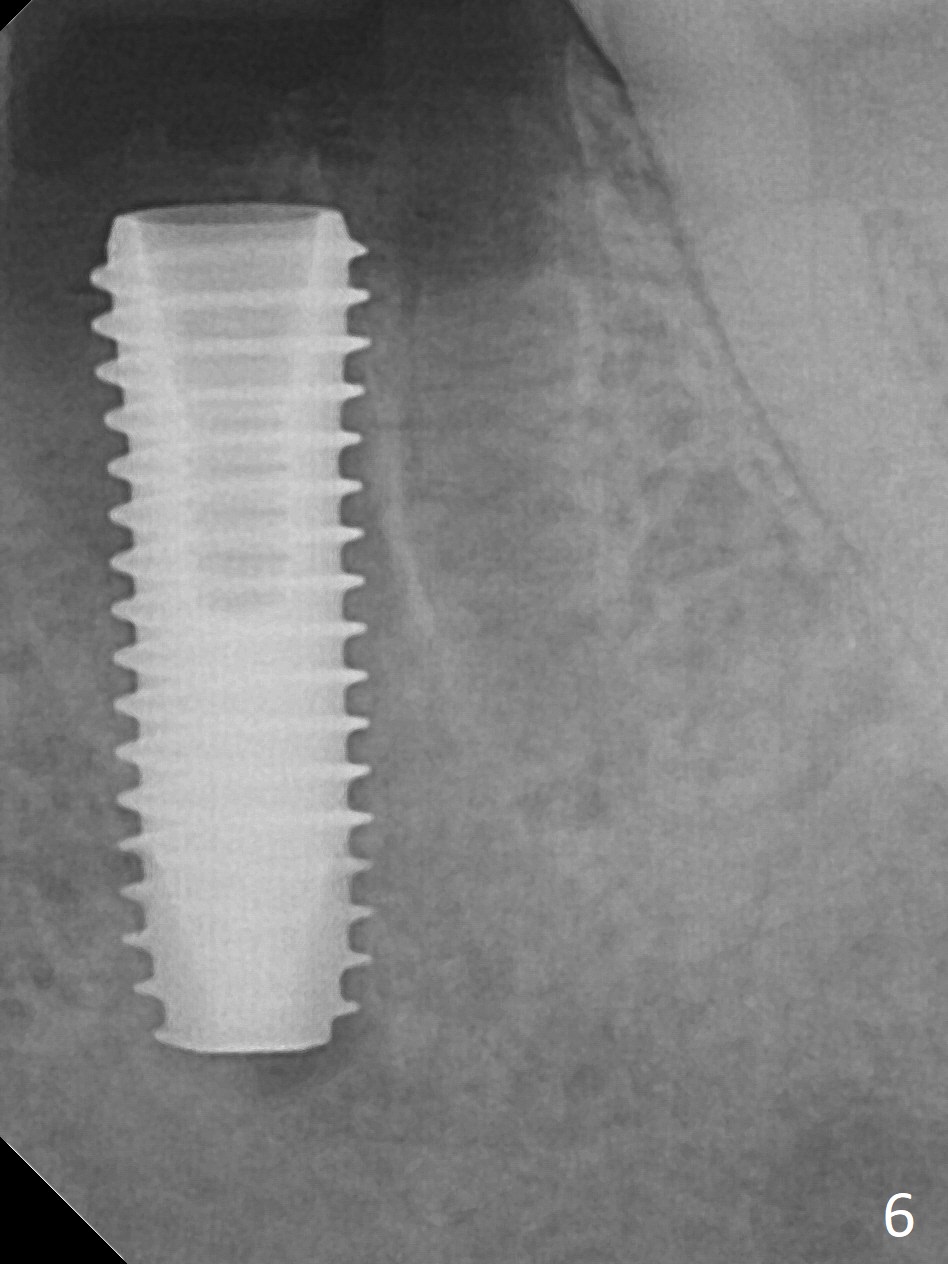

When the patient returns 9 months later, there is severe buccal gingival recession and abscess at #19 (Fig.1 *) with large mesial periradicular radiolucency (Fig.2 *). The septum is thin and the buccal crest is low after extraction (Fig.3 * (mesial root vertical fracture)). Osteotomy is initiated in the mesial socket immediately against the septum (Fig.4.5) with ~ 5 mm in the native bone. Due to severe buccal plate resorption, a shorter implant is placed (Fig.6; 5x15 mm in stead of 18 mm). There is at least 2 mm gap buccally for Vanilla Graft, which is also placed next to the implant and the neighboring root (Fig.7 *). There is clearance from the Inferior Alveolar Canal (Fig.8 red dashed line). Both the mesial and distal sockets heal 5.5 months postop (Fig.9), although the apical portion of the distal socket was not filled with allograft (Fig.7). The implant was placed mesial. The straight abutment (6.5x4(4) mm) (Fig.10) is changed to an angled one (5.5 x15 degrees 3 mm cuff (Fig.11)) before impression. The implant is also placed buccally. Therefore the implant position is far more important than its length. The abutment is retightened 2.5 months post cementation, which is related to mesiobuccal placement of the implant (Fig.12). An ideal trajectory is determined by drawing 2 horizontal lines (at crestal and apical levels: red lines in Fig.13), finding a central point of each line (vertical short line) and joining these 2 central points (Fig.14 pink line). In fact the ideal osteotomy should have been established distal to the septum in this case. Guided surgery may alleviate the issue. The crown is not loose, but the patient feels that the implant tooth cannot sustain mastication. In fact the screw is removed with hand driver (not wrench). The abutment hex is rounded and worn. A new 5.5x4(4) mm abutment is placed (without knowledge of previous use of an angled abutment) with mesial reduction to reduce undercut and buccodistal margin lowered to reduce gingival embrasure. It is that the straight abutment could decrease the chance of screw loosening. Otherwise the implant has to be removed for better trajectory.